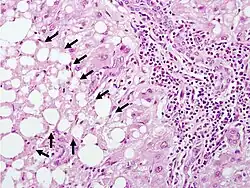

Widespread necrosis in the central venule regions of the liver acinus. Lipid droplets have merged to form lipid lakes.

Mostly viable hepatocytes in the portal area (zone 1) of the liver acinus, with arrows pointing to a necrotic zone on the edge

These H&E pathology slides were taken from an acetaminophen poisoning case involving an adult with a history of alcohol abuse. Case contributed by Dr. Linda Ferrell, UCSF, Department of Pathology.

The second phase occurs between 24 hours and 72 hours following overdose and consists of signs of increasing liver damage. In general, damage occurs in liver cells as they metabolize the paracetamol. Hallmark pathology on liver biopsy includes regions of coagulative necrosis in zone 3 of the liver acinus, around the central venules, as these hepatocytes have higher concentrations of cytochrome P450 enzymes compared to zone 1 hepatocytes surrounding the portal venule of the acinus. Remaining viable hepatocyes frequently show ballooning injury and steatosis. [13] The individual may experience right upper quadrant abdominal pain. The increasing liver damage also changes biochemical markers of liver function; International normalized ratio (INR) and the liver transaminases ALT and AST rise to abnormal levels.[14] Acute kidney failure may also occur during this phase, typically caused by either hepatorenal syndrome or multiple organ dysfunction syndrome. In some cases, acute kidney failure may be the primary clinical manifestation of toxicity. In these cases, it has been suggested that the toxic metabolite is produced more in the kidneys than in the liver.[15]